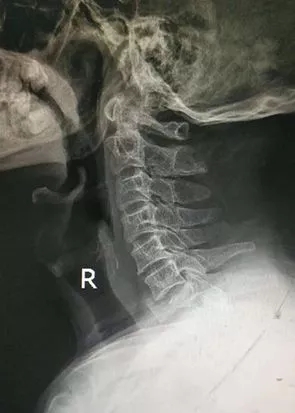

到医院后,经医生检查并结合影像学结果诊断,刘大叔颈7椎体压缩性骨折并椎管狭窄、颈椎间盘脱出、左侧肢体伴有瘫痪,急需颈椎手术治疗。

术前X片

颈椎是人的生命之枢,统领全身的血管和神经,颈椎同时伴多部位骨折很危险也很罕见。特别是术中螺钉穿行的部位旁边是为大脑提供血液的椎动脉,手术稍有不慎,都会引起严重后果,手术难度极高,这要求主刀医生必须拥有脊柱外科扎实的基本功和丰富的手术经验。医院副院长脊柱科首席专家谢军、脊柱科主任李伟雄等组成的医护团队,认真评估患者术前病情,经过会诊,制定详细的麻醉手术方案及术后的康复流程。与此同时,专家团队积极完善各种术前准备,择期在全麻下为刘大叔行颈7椎体次全切﹢椎管扩大﹢钛笼植骨融合前路﹢自锁钢板内固定手术。经过两个小时的紧张手术,专家团队克服了颈椎骨折、脱位、压迫脊髓椎动脉等巨大风险,术后患者肢体功能恢复良好,头脑清醒,没有出现任何其他并发症。